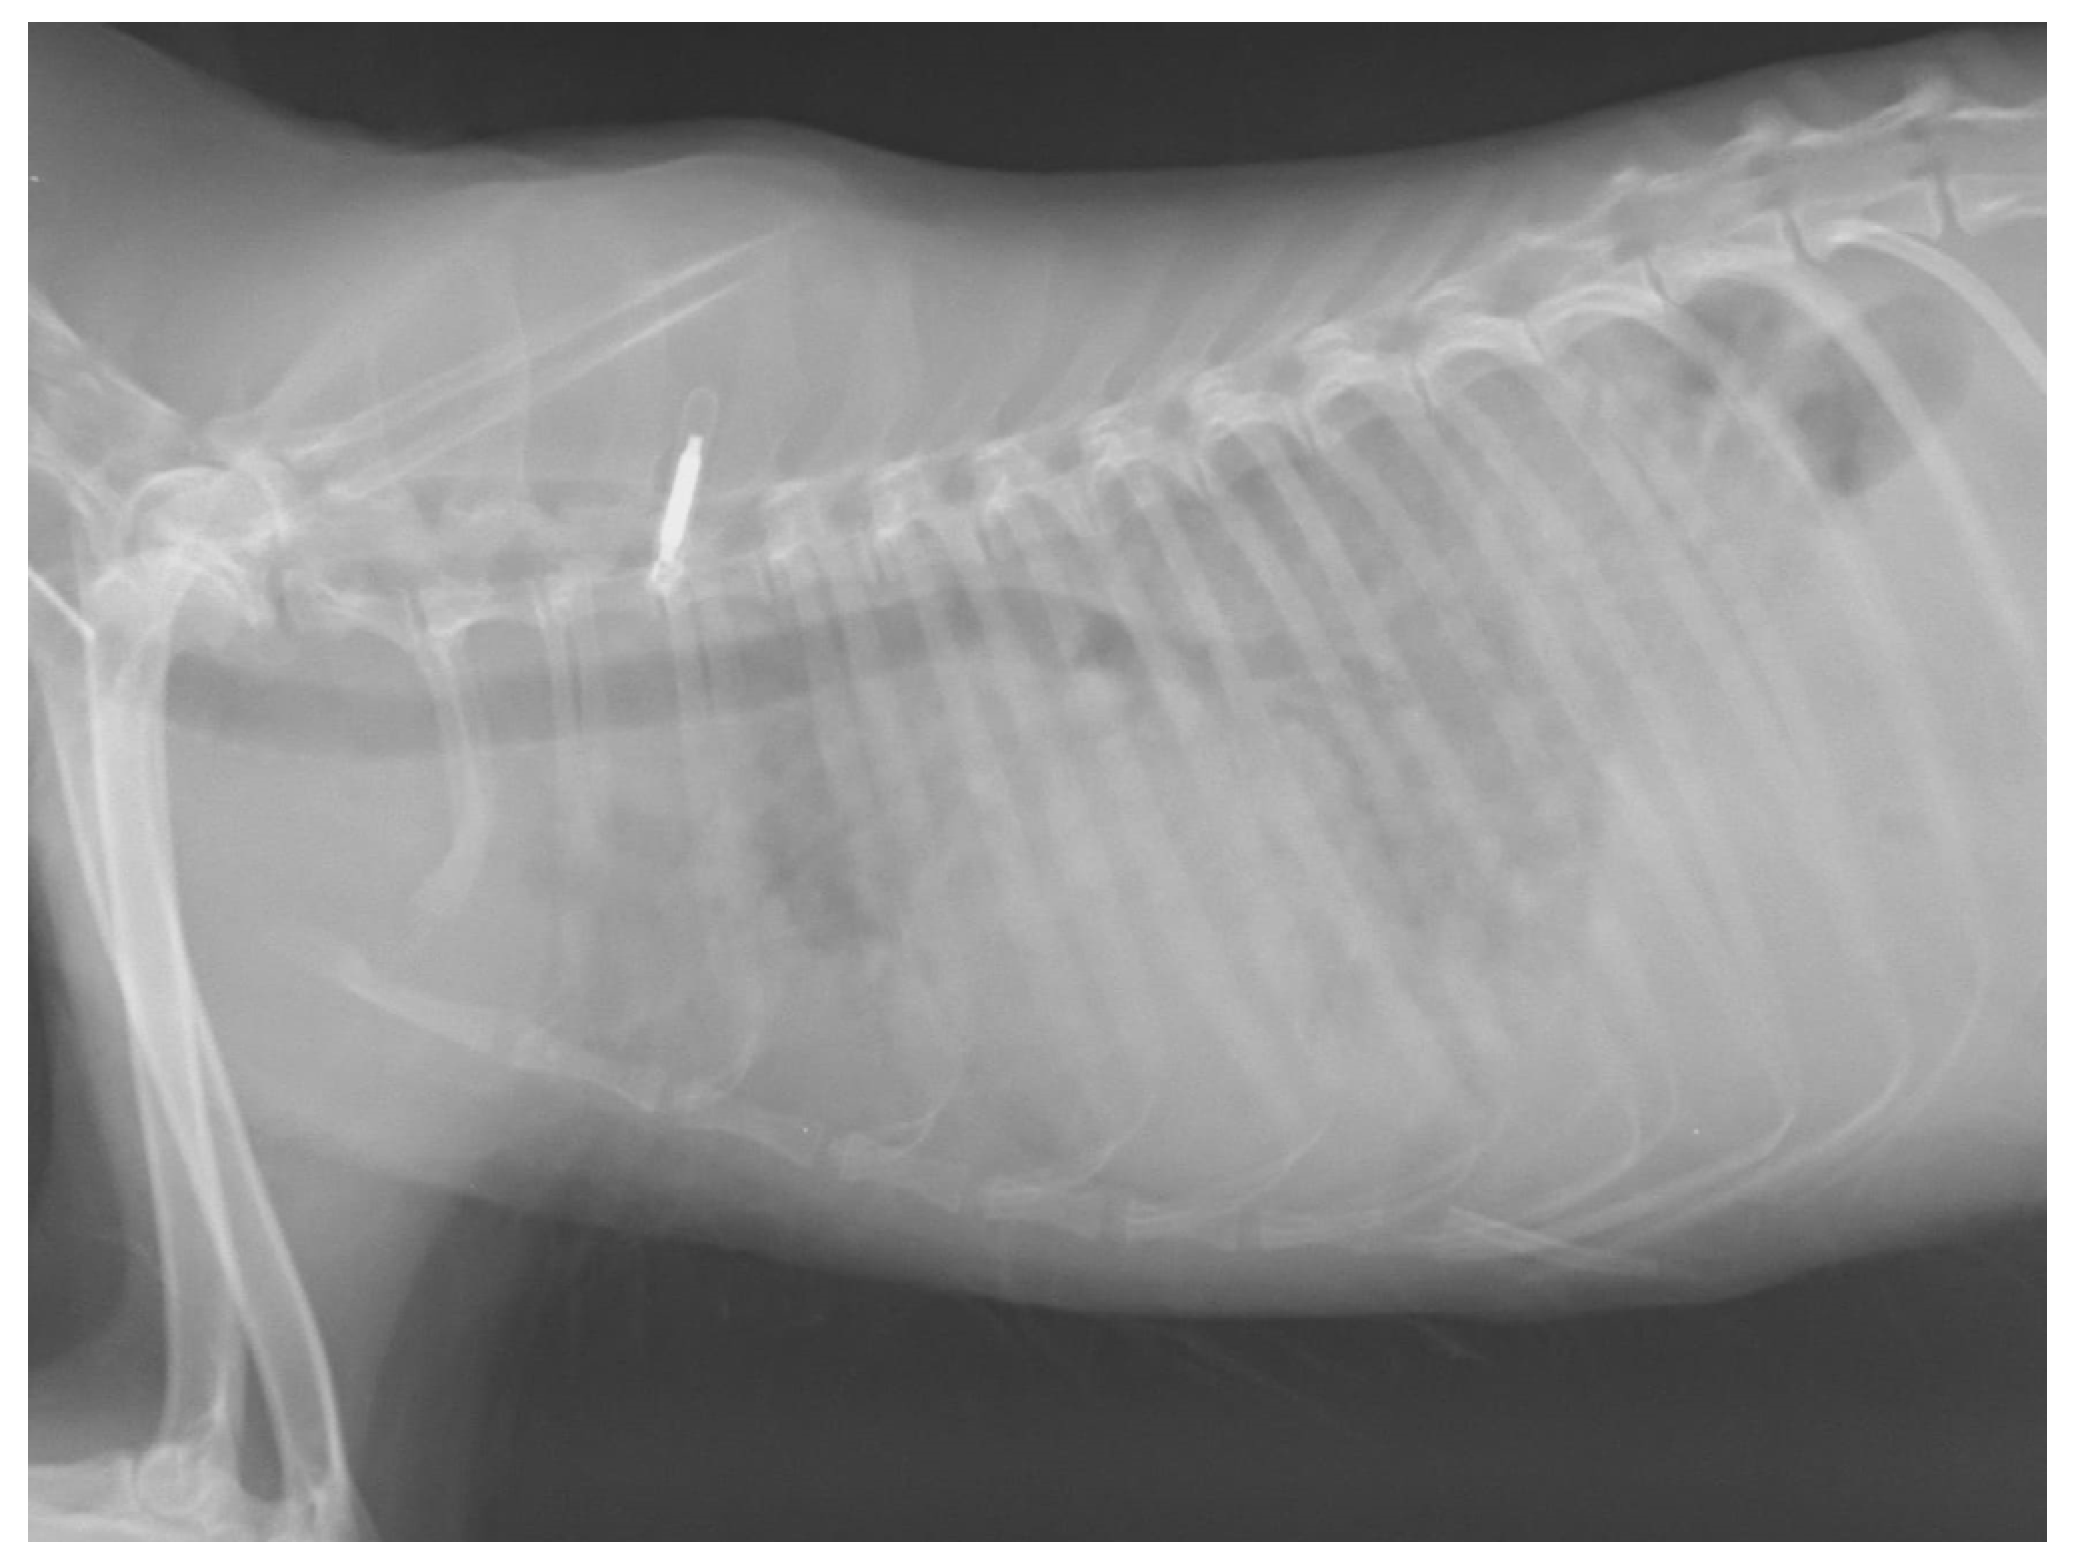

The fennec, a 14 month-old female species born at Bioparco, used to live in a semi-natural pen with other five conspecific individuals and was brought to the Istituto Zooprofilattico Sperimentale del Lazio e della Toscana “M. Aleandri” (IZSLT) for post mortem examination after being euthanised. One month before death, it had presented weakness, ataxia and paraparesis. Haemochromocytometric tests revealed mild lymphocytosis. It was treated with a corticosteroid (prednisolone, 1 mg/kg/die) and antibiotic therapy (Enrofloxacin, 5 mg/kg/die) for 3 weeks. Respiratory signs, such as cough and severe dyspnoea, emerged 2 days before death. After the appearance of these last signs, thoracic radiograph was performed, showing a diffuse nodular broncho-interstitial lung pattern (Figure 1). Due to serious clinical condition and lack of improvement with the treatment protocol, it was decided to carry out euthanasia.

Figure 1.

Thoracic radiograph of the fennec. Image shows lateral radiographic projection of the chest in which a diffuse nodular broncho-interstitial lung pattern can be observed.